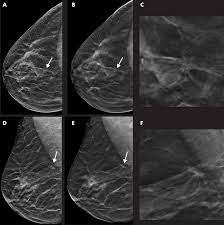

What Does Cancer Look Like On Mammogram : Mammography 3d Mammography Tomosynthesis Densebreast Info Inc / The rate of breast cancers discovered as dcis is thought to be increasing, but this is partially a testament to the effectiveness of mammographic breast cancer screening programs.ductal carcinoma in situ represents up to 30% of all new cases of breast cancer discovered by breast cancer screening.. Regular mammograms are the best tests doctors have to find breast cancer early, sometimes up to three years before it can be felt. In this mammogram image, the breast calcifications are in ductal patterns. Any area that does not look like normal tissue is a possible cause for concern. Calcifications are tiny flecks of calcium — like grains of salt — in the soft tissue of the breast that can sometimes indicate the presence of an early breast cancer. Any area that does not look like normal tissue is a possible cause for concern.

Invasive breast cancer can appear as a white patch or mass on a mammogram. The tumor cells don't stay within the clear borders of the mass, but instead invade the nearby breast tissue. You may notice dimpling or pitting, and the skin on your breast. A rash isn't the only visual symptom of inflammatory breast cancer. Regular mammograms are the best tests doctors have to find breast cancer early. In a normal breast, a mammogram shows normal skin dark grey fat and lighter grey breast tissue. According to the american cancer society (acs), the most common sign of breast cancer is a new lump or mass in the breast. How can mammograms be used? Cancers may be seen as masses (like a ball, but usually with an irregular shape), areas of asymmetry that resemble normal tissue, calcifications (white specks), and/or areas of architectural distortion (imagine the puckering caused by pulling a thread in a piece of fabric). In this mammogram image, the breast calcifications are in ductal patterns. Healthy mammograms can still vary in appearance. It is important to bear in mind that most women who are asked to come back after. Any area that does not look like normal tissue is a possible cause for concern.

Basic Information About Mammograms from aboutcancer.com What does cancer look like on a mammogram? Cancers may be seen as masses (like a ball, but usually with an irregular shape), areas of asymmetry that resemble normal tissue, calcifications (white specks), and/or areas of architectural distortion (imagine the puckering caused by pulling a thread in a piece of fabric). Any area that does not look like normal tissue is a possible cause for concern. A mammogram can show breast changes such as calcifications, masses, or other symptoms that might be cancer. Cancers may be seen as masses (like a ball, but usually with an irregular shape), areas of asymmetry that resemble normal tissue, calcifications (white specks), and/or areas of architectural distortion (imagine the puckering caused by pulling a thread in a piece of fabric). Any area that does not look like normal tissue is a possible cause for concern. But it's not uncommon that they see something that looks like it might be cancer —a finding that could end up being completely normal, but that needs to be further tested to be sure. Regular mammograms are the best tests doctors have to find breast cancer early, sometimes up to three years before it can be felt.

Ibc symptoms are caused by cancer cells blocking lymph vessels in the skin causing the breast to look inflamed. symptoms include breast swelling, purple or red color of the skin, and dimpling or thickening of the skin of the breast so that it may look and feel like an orange peel. What does cancer look like on a mammogram? Cancers may be seen as masses (like a ball, but usually with an irregular shape), areas of asymmetry that resemble normal tissue, calcifications (white specks), and/or areas of architectural distortion (imagine the puckering caused by pulling a thread in a piece of fabric). Tumors may be benign or cancerous. According to the american cancer society (acs), the most common sign of breast cancer is a new lump or mass in the breast. Suspicious findings include clusters of tiny microcalcifications or a density/mass with irregular or spiculated margins. Any area that does not look like normal tissue is a possible cause for concern. This can make it harder for your radiologist to spot signs of breast cancer, since dense tissue and tumors both look white in mammogram images. Breast cancer and some noncancerous (benign) breast conditions can appear white on a mammogram. This is considered an abnormal mammogram, but not necessarily one that's indicative of cancer. Invasive breast cancer can appear as a white patch or mass on a mammogram. By the time it's diagnosed, it usually has grown into the skin of your breast. What does an abnormal mammogram look like?

Ai Assisted Radiologists Can Detect More Breast Cancer With Reduced False Positive Recall Imaging Technology News from www.itnonline.com Breast cancer and some noncancerous (benign) breast conditions can appear white on a mammogram. By the time it's diagnosed, it usually has grown into the skin of your breast. The outer edges of these cells look fuzzy or spiky (called spiculated). They will look carefully at the mammogram to interpret the results. The doctor reading your mammogram will be looking for different types of breast changes, such as small white spots called calcifications, larger abnormal areas called masses, and other suspicious areas that could be signs of cancer. The appearance of normal breast tissue on a mammogram varies from person to person, and no two mammograms look the same. Cancers may be seen as masses (like a ball, but usually with an irregular shape), areas of asymmetry that resemble normal tissue, calcifications (white specks), and/or areas of architectural distortion (imagine the puckering caused by pulling a thread in a piece of fabric). According to the american cancer society (acs), the most common sign of breast cancer is a new lump or mass in the breast.